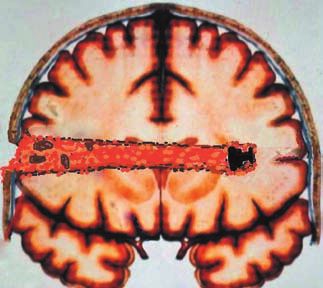

Ранение представляло собой слепое диаметральное проникающее повреждение правой височно-теменной области головного мозга с дырчатым переломом правой теменной кости (ил. 1). При рентгенологическом обследовании и компьютерной томографии черепа в левой височной доле была обнаружена пуля (ил. 2, 3).

Ил. 3. Схема ранения головного мозга. В области входной раны видны отломки височной кости, в конце раневого канала – пуля патрона 18х45Т